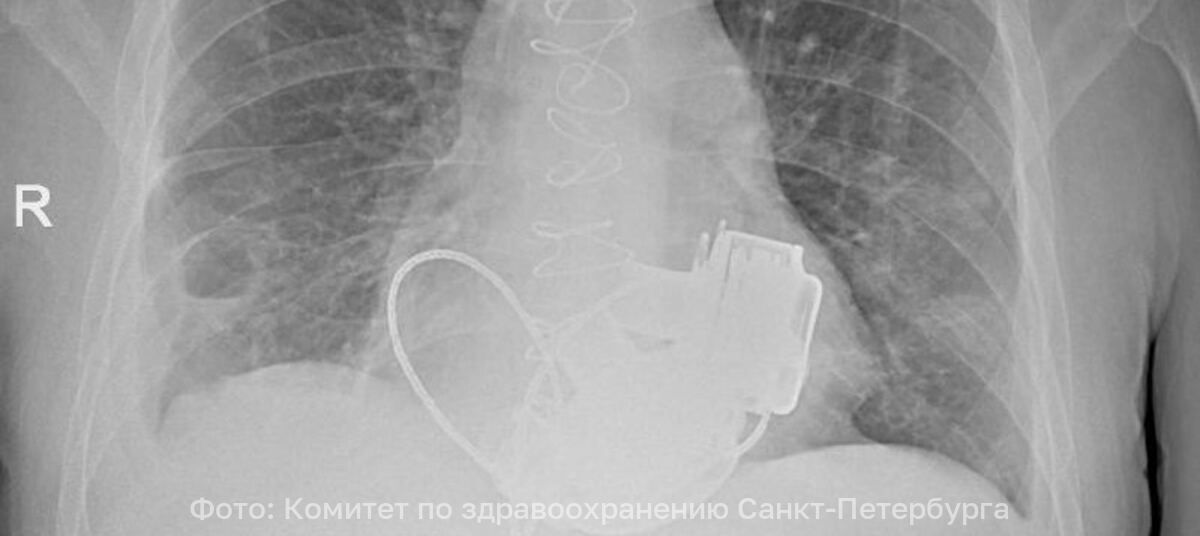

Пульса нет вообще, а вместо сердца — два пламенных мотора: в России впервые пациенту имплантировали оба желудочка - Новости Калининграда | Фото: Комитет по здравоохранению Санкт-Петербурга

Фото: Комитет по здравоохранению Санкт-Петербурга

В Санкт-Петербурге врачи готовят к выписке пациента, который теперь живёт без пульса. В конце ноября 2025 года 36-летнему мужчине имплантировали одновременно левый и правый искусственные желудочки сердца. Об этом рассказали в городском комитете по здравоохранению.

По словам главного врача Мариинской больницы Игоря Реутского, когда Антон поступил в стационар, показатели работы сердца были такими, будто человек уже не жив, а мёртв. При этом из-за сопутствующих осложнений трансплантация сердца была невозможна.

«Операция продолжалась около 4 часов. Для наших специалистов самым сложным было синхронизировать работу двух искусственных желудочков сердца, но с этой задачей мы успешно справились. Это доказывает высокий уровень развития кардиохирургии в нашем городе». — отметил главный внештатный специалист по сердечно-сосудистой хирургии Санкт-Петербурга Геннадий Хубулава.

Врачи надеются теперь вновь встретиться с Антоном, так как имплантация искусственных желудочков — «мостик» к трансплантации сердца, которую пациент теперь сможет дождаться.